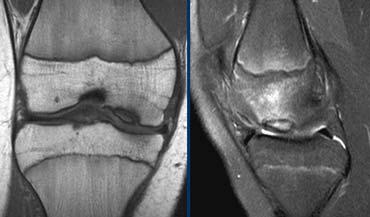

Viêm xương sụn bóc tách

Chẩn đoán Viêm xương sụn bóc tách thường được thực hiện trên X-quang.

Câu hỏi đặt ra khi chụp MRI là tổn thương ổn định hay không ổn định.

Ca lâm sàng bên trái là không ổn định vì hai lý do:

– Các nang nhỏ ở nền tổn thương (mũi tên đỏ)

– Quan trọng hơn là có dịch ở nền tổn thương (mũi tên xanh)

Lưu ý rằng lớp dịch này khác với AVN, nơi dịch nằm giữa sụn và xương.

Viêm xương sụn bóc tách không ổn định. Dấu hiệu duy nhất có giá trị để chẩn đoán OD không ổn định là dịch (mũi tên vàng), không phải phù tủy hay gián đoạn bề mặt xương sụn (mũi tên xanh lá).

Các dấu hiệu không có giá trị trong việc phân biệt OD ổn định và không ổn định bao gồm:

– Phù tủy xương (có thể gặp trong cả hai trường hợp)

– Gián đoạn bề mặt xương sụn.

Vì vậy, ca lâm sàng bên trái là không ổn định vì có dịch ở nền tổn thương.

Ca lâm sàng bên trái cho thấy viêm xương sụn bóc tách với phù tủy xương và gián đoạn bề mặt xương sụn.

Tuy nhiên, vì không có dịch, chúng ta không thể xác định đây là tổn thương ổn định hay không ổn định.

Trong phẫu thuật, tổn thương viêm xương sụn bóc tách được xác nhận là ổn định.

Trong những trường hợp không thể xác định tổn thương ổn định hay không ổn định, chụp MRI khớp có thuốc tương phản từ (MR-arthrogram) rất có giá trị.

Chúng ta tìm kiếm dấu hiệu Gadolinium thấm vào xung quanh tổn thương xương sụn.